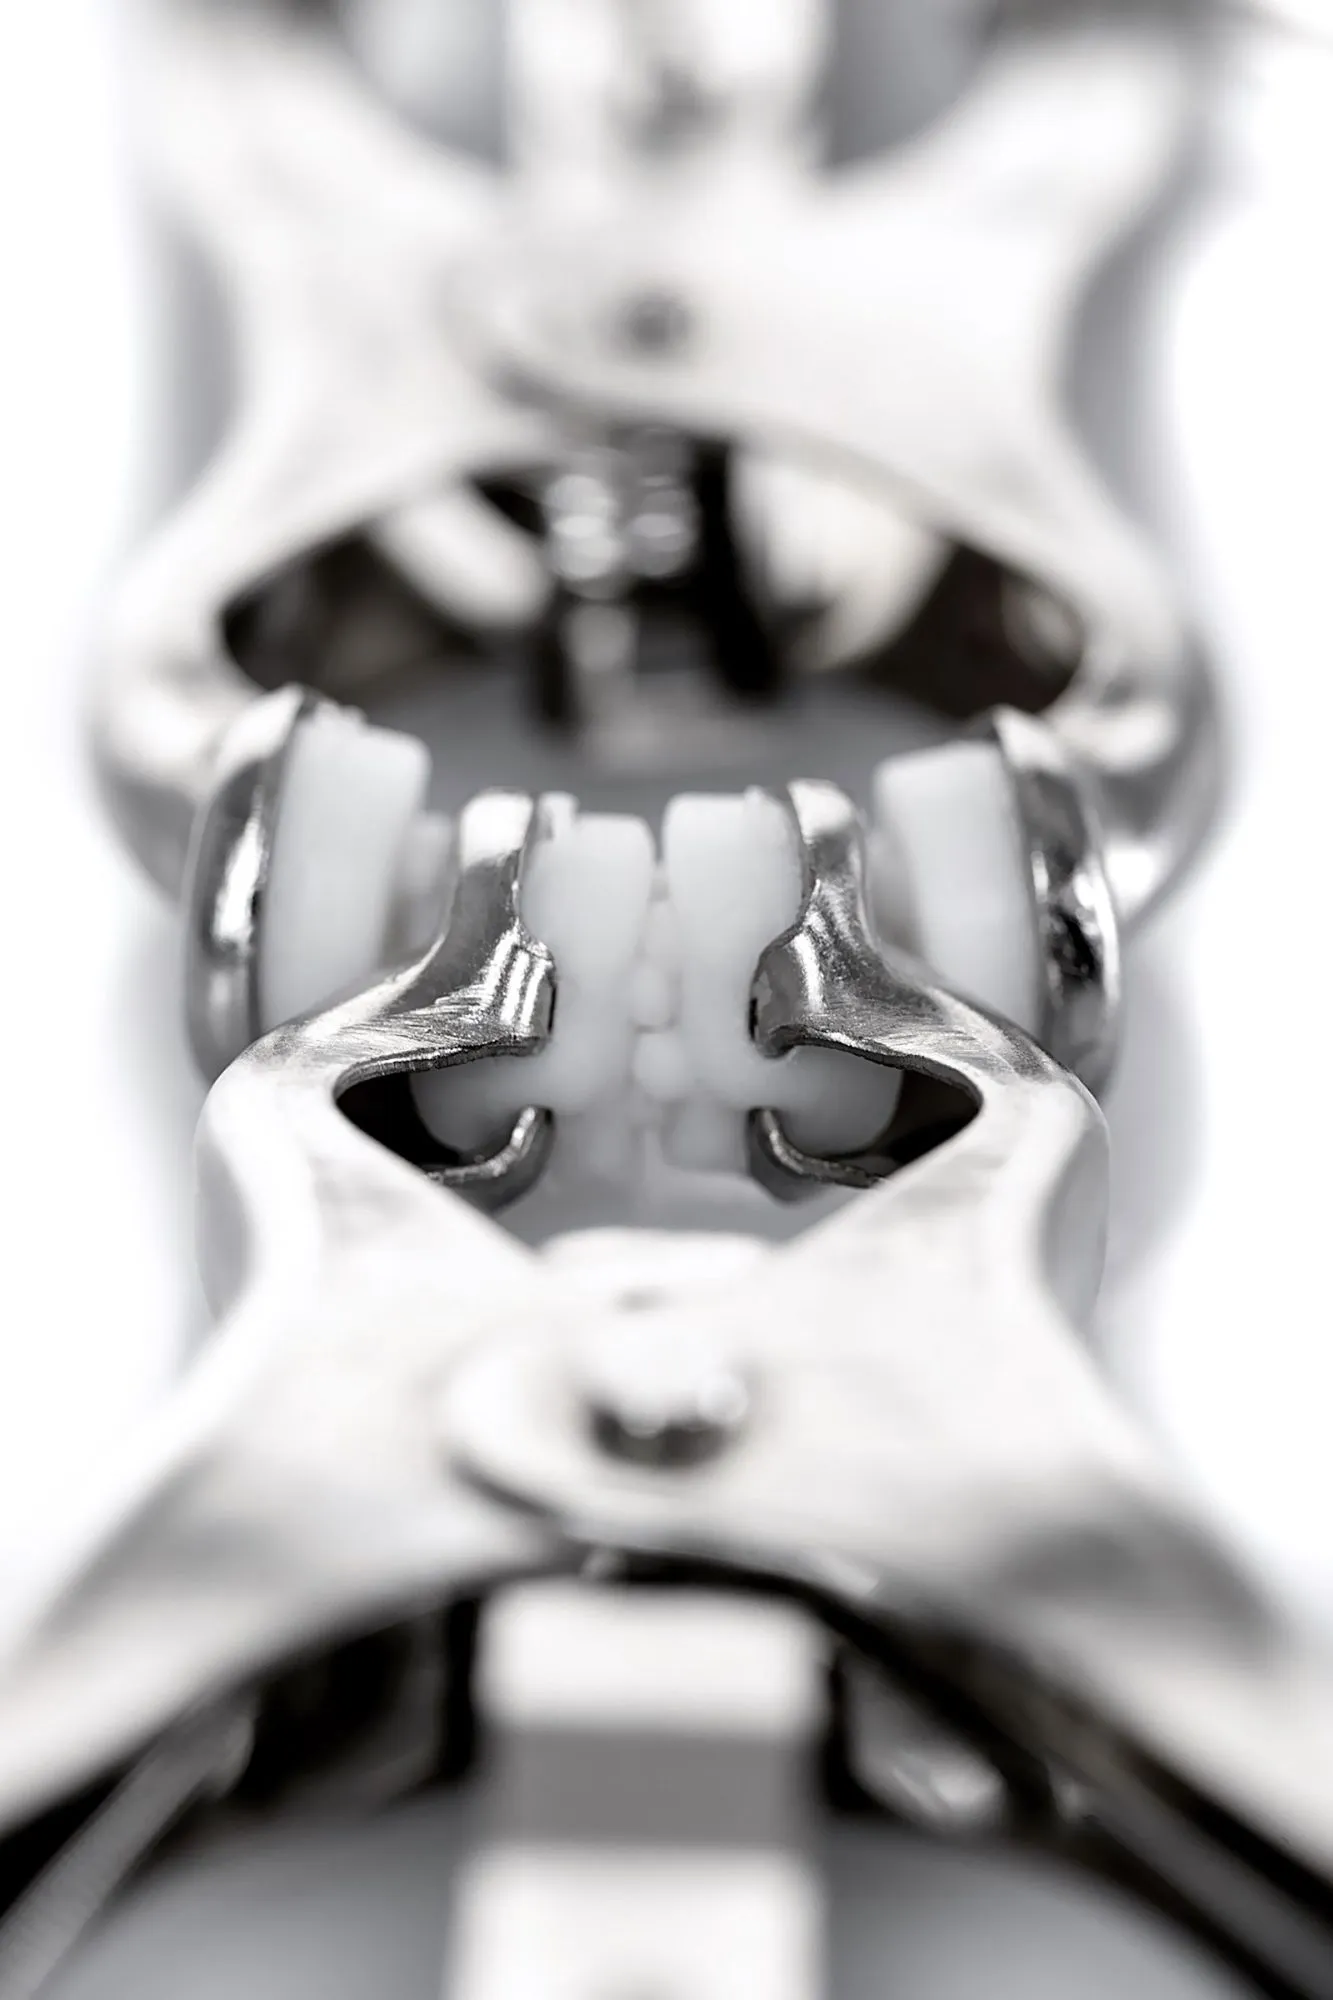

| ID | 132827 |

| Материал | Металл |